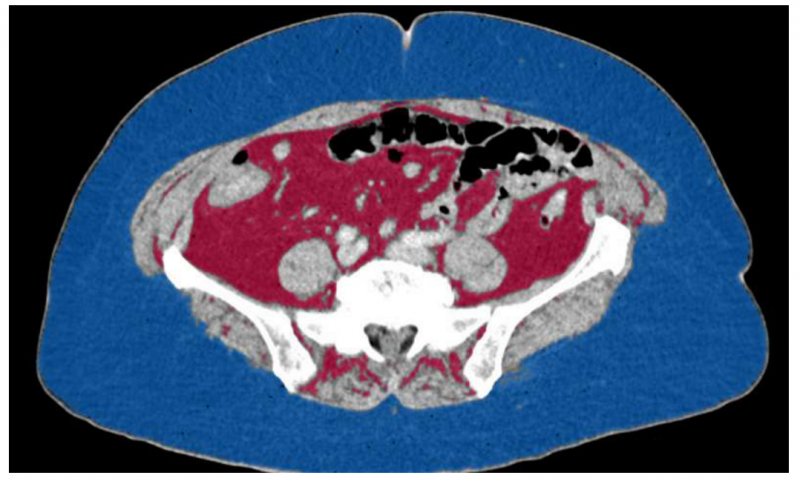

根据圣路易斯华盛顿大学医学院研究人员的一项新研究,腹部脂肪影响肾癌女性存活率,但不影响男性。研究人员分析了145名男性肾癌和77名女性肾癌患者的影像,结果发现,50%有腹部脂肪的女性肾癌患者在确诊后3年半内死亡,而一半以上腹部脂肪少的肾癌女性在10年后仍然活着。对于男性来说,腹部脂肪的含量对于存活期没有什么区别。评估身体脂肪的大多数方法都依赖于一个人的身高